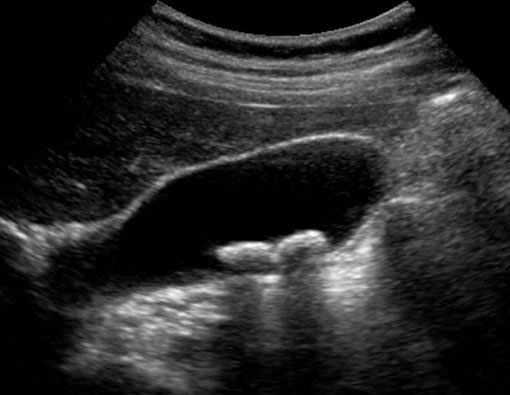

EHO-SONOGRAFIJA KALKULOZE ŽUČNE KESE

EHO-SONOGRAFIJA KALKULOZE ŽUČNE KESE SA HOLECISTITISOM